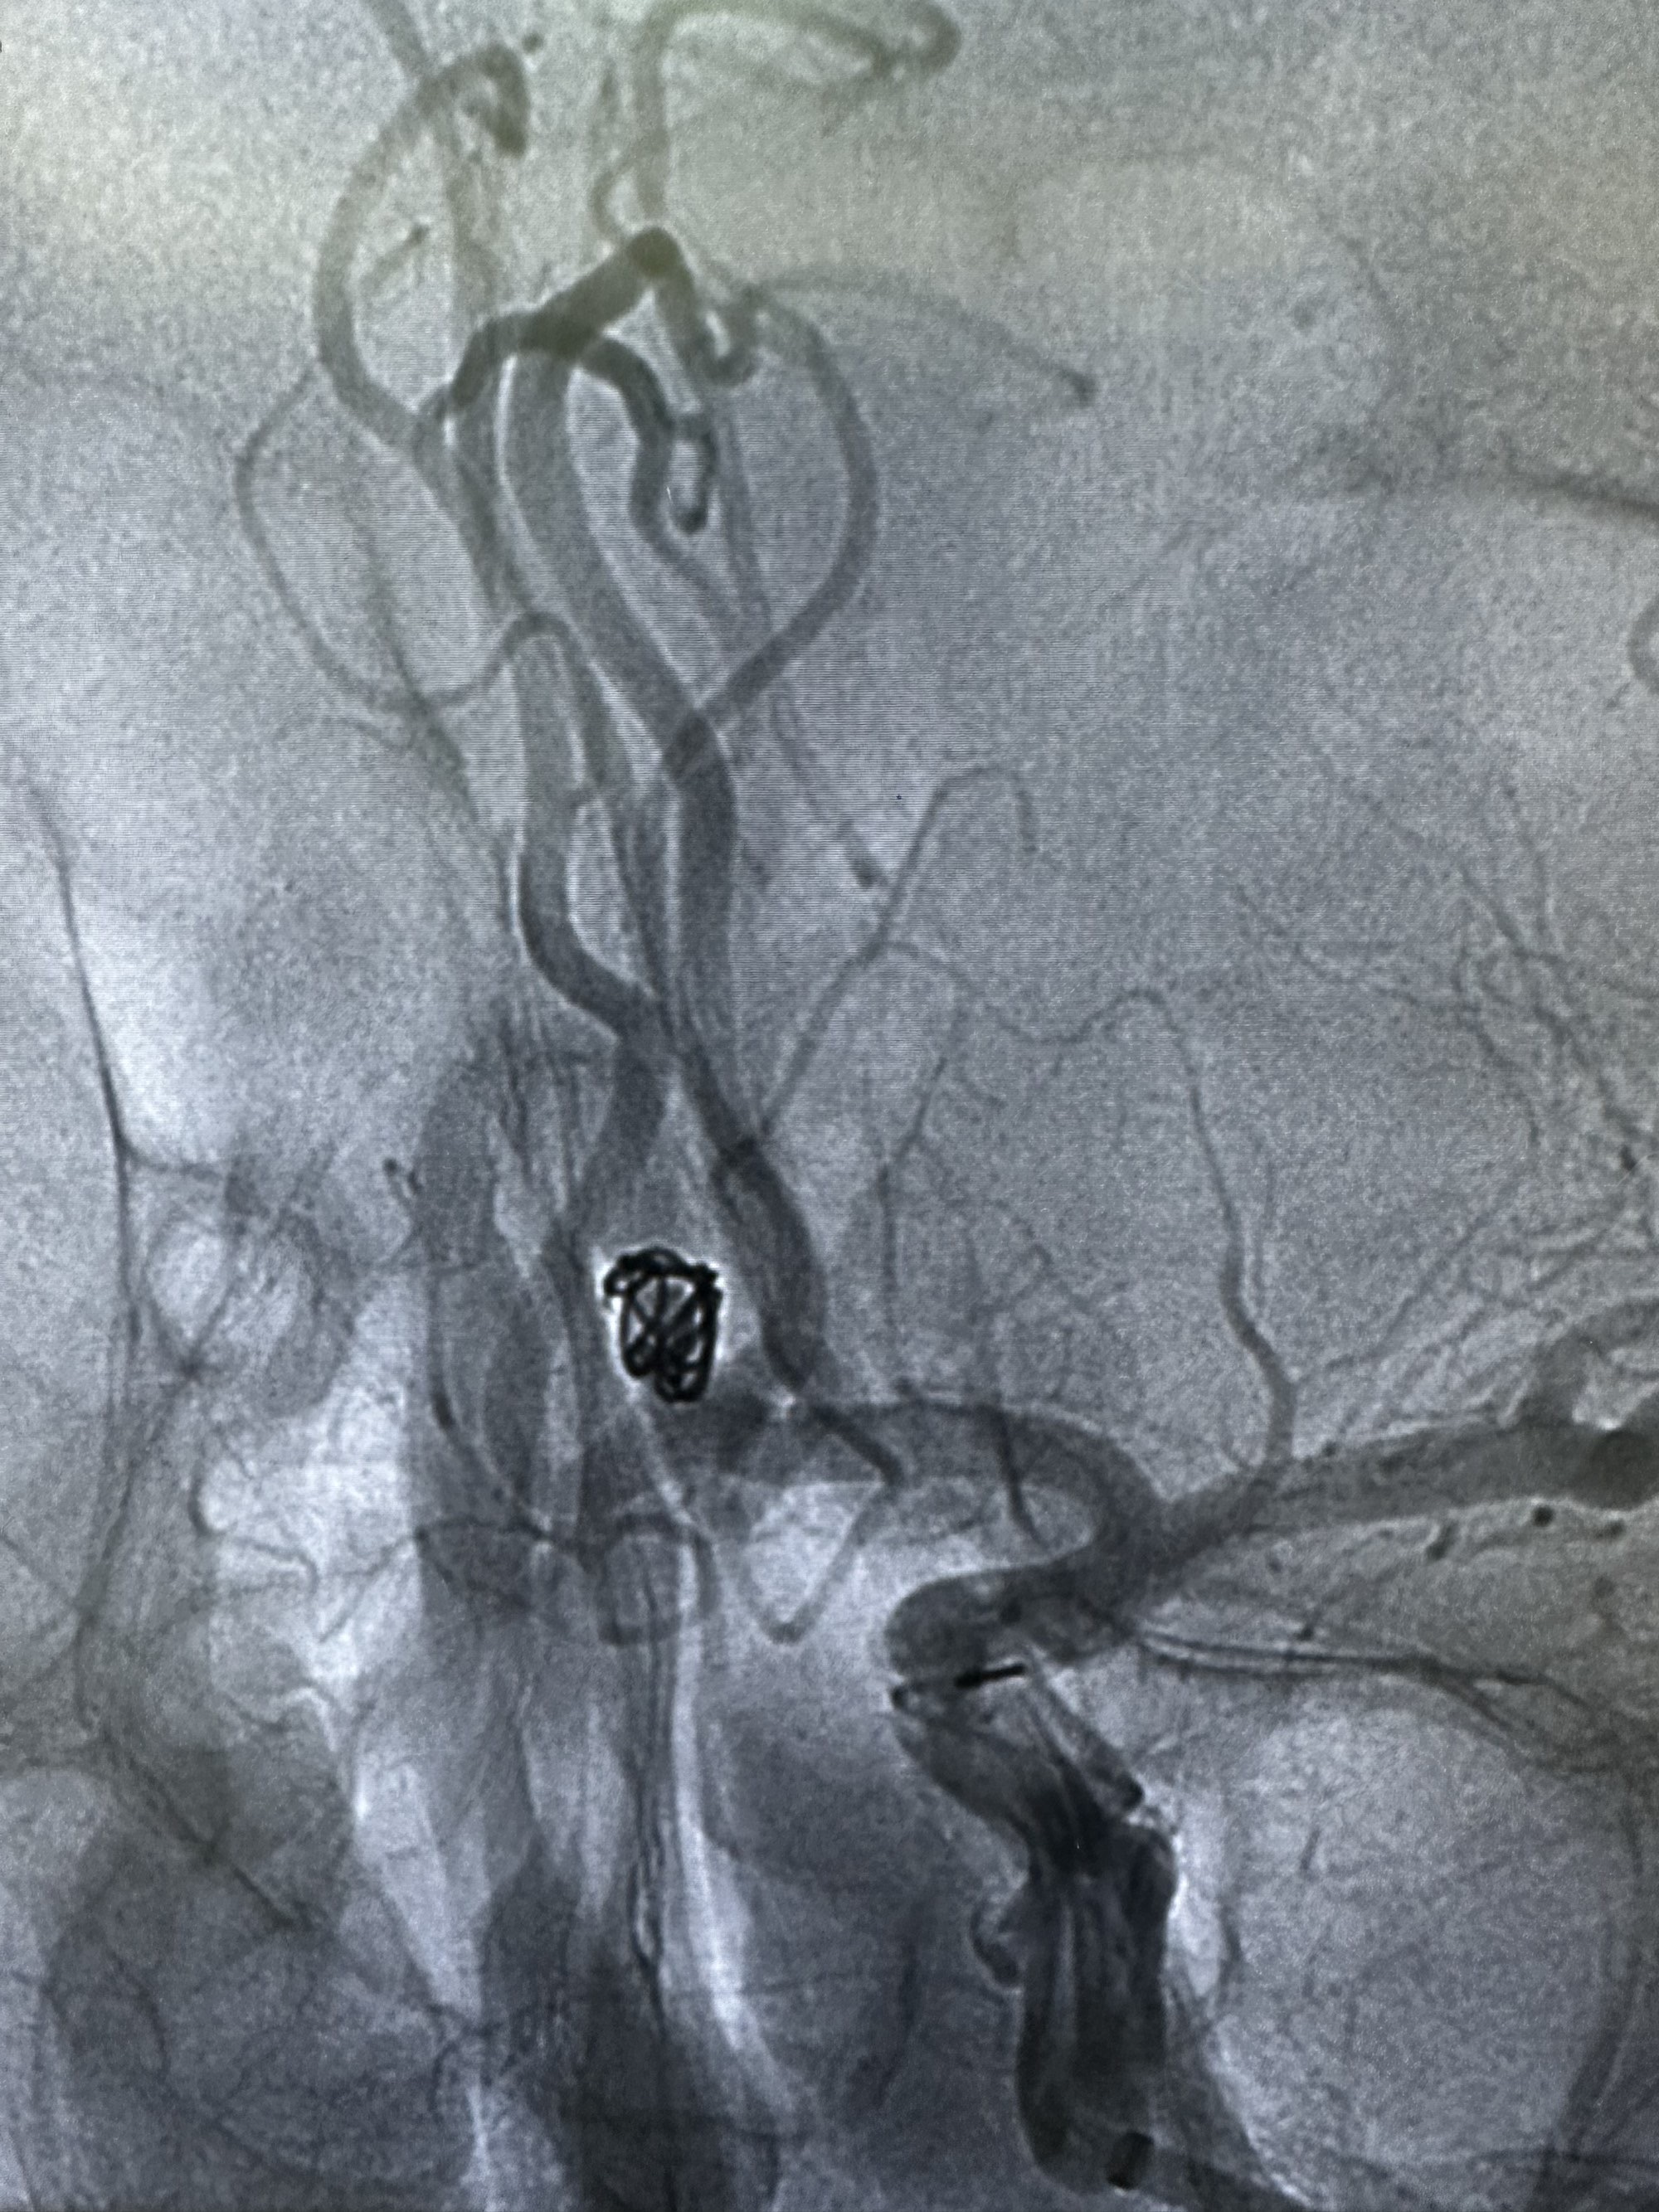

侧位